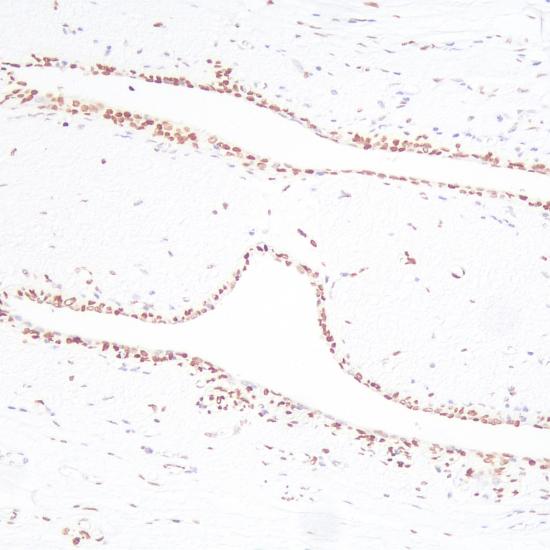

BRCA1抗體試劑(免疫組織化學法) 閩廈械備20190063號

• 預處理:

熱修復

• 陽性部位:

細胞核

• 陽性對照:

乳腺癌

• 適用組織:

石蠟

• 免疫顯色試劑:

iVision?

• 產(chǎn)品編號:

AM0437

• 種屬來源:

鼠單抗

• 克隆號:

MS110

BRCA1是乳腺癌的易感基因之一,BRCA1功能丟失增加乳腺癌和卵巢癌的易感性。該抗體主要用于乳腺癌和卵巢癌的研究。